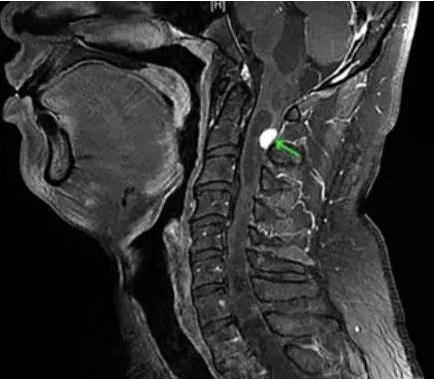

医師が首の後ろに腫瘍を発見したのは3回目の診察のときだった。そしてこの神経の役割は、呼吸運動を完成させるために脳から横隔膜にインパルスを伝えることである。。

だから、この男の呼吸神経が圧迫されたとき、横隔膜に間違った信号が送られることになった。横隔膜の不随意収縮を引き起こす。そのため、患者は絶えずげっぷをする。